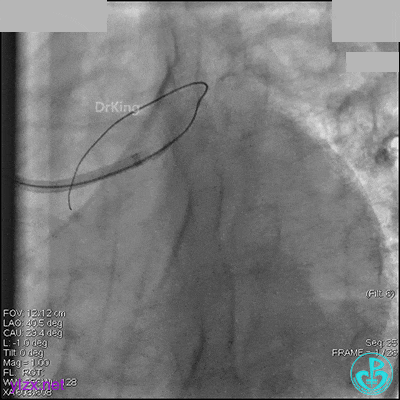

1周后再次上台,右冠脉3级血流,3段局限性严重狭窄,内膜模糊,应该是上次操作夹层遗留下的血肿。